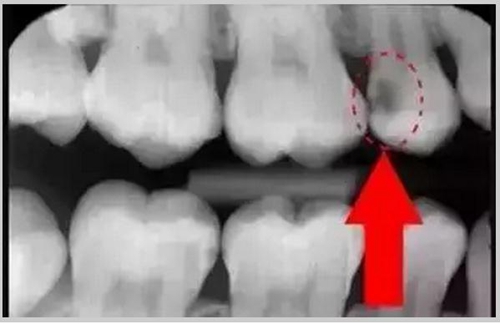

圈出來的地方或多或少都有點齲齒,但是有些你并不能看見。這些齲齒還淺不會讓你有什么感覺,頂多吃東西塞牙,和冷水敏感而已。

暗的部位說明齲齒已經(jīng)非常嚴重了!

上面這個是接近牙髓了!